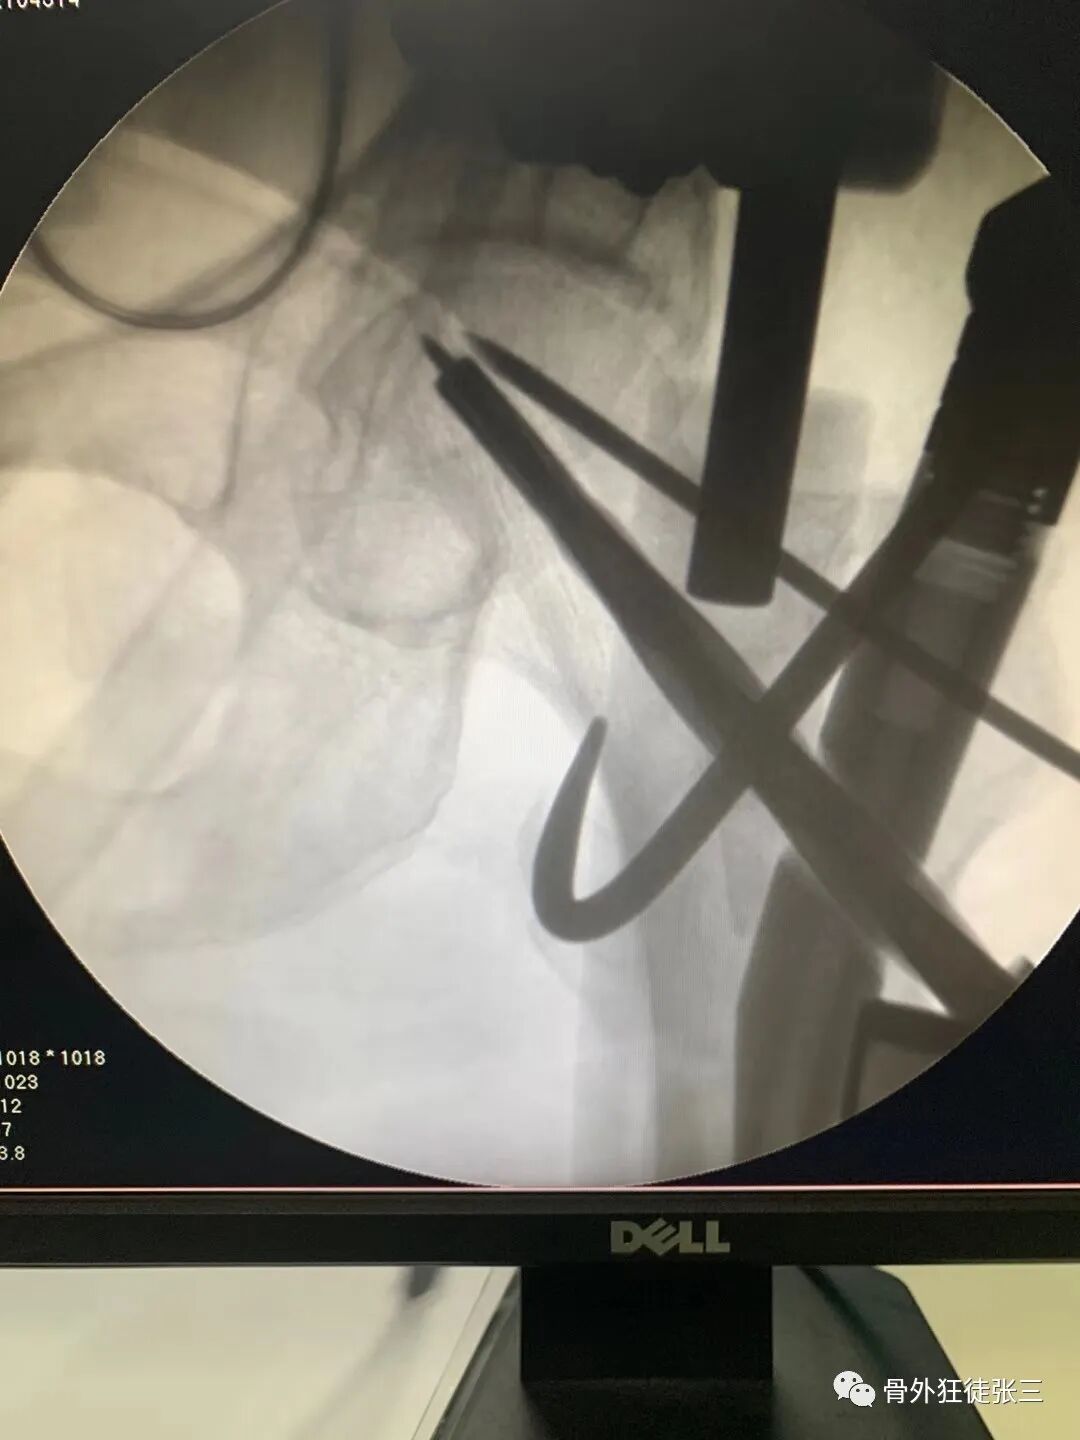

病例49,陈旧性月骨脱位,克氏针固定